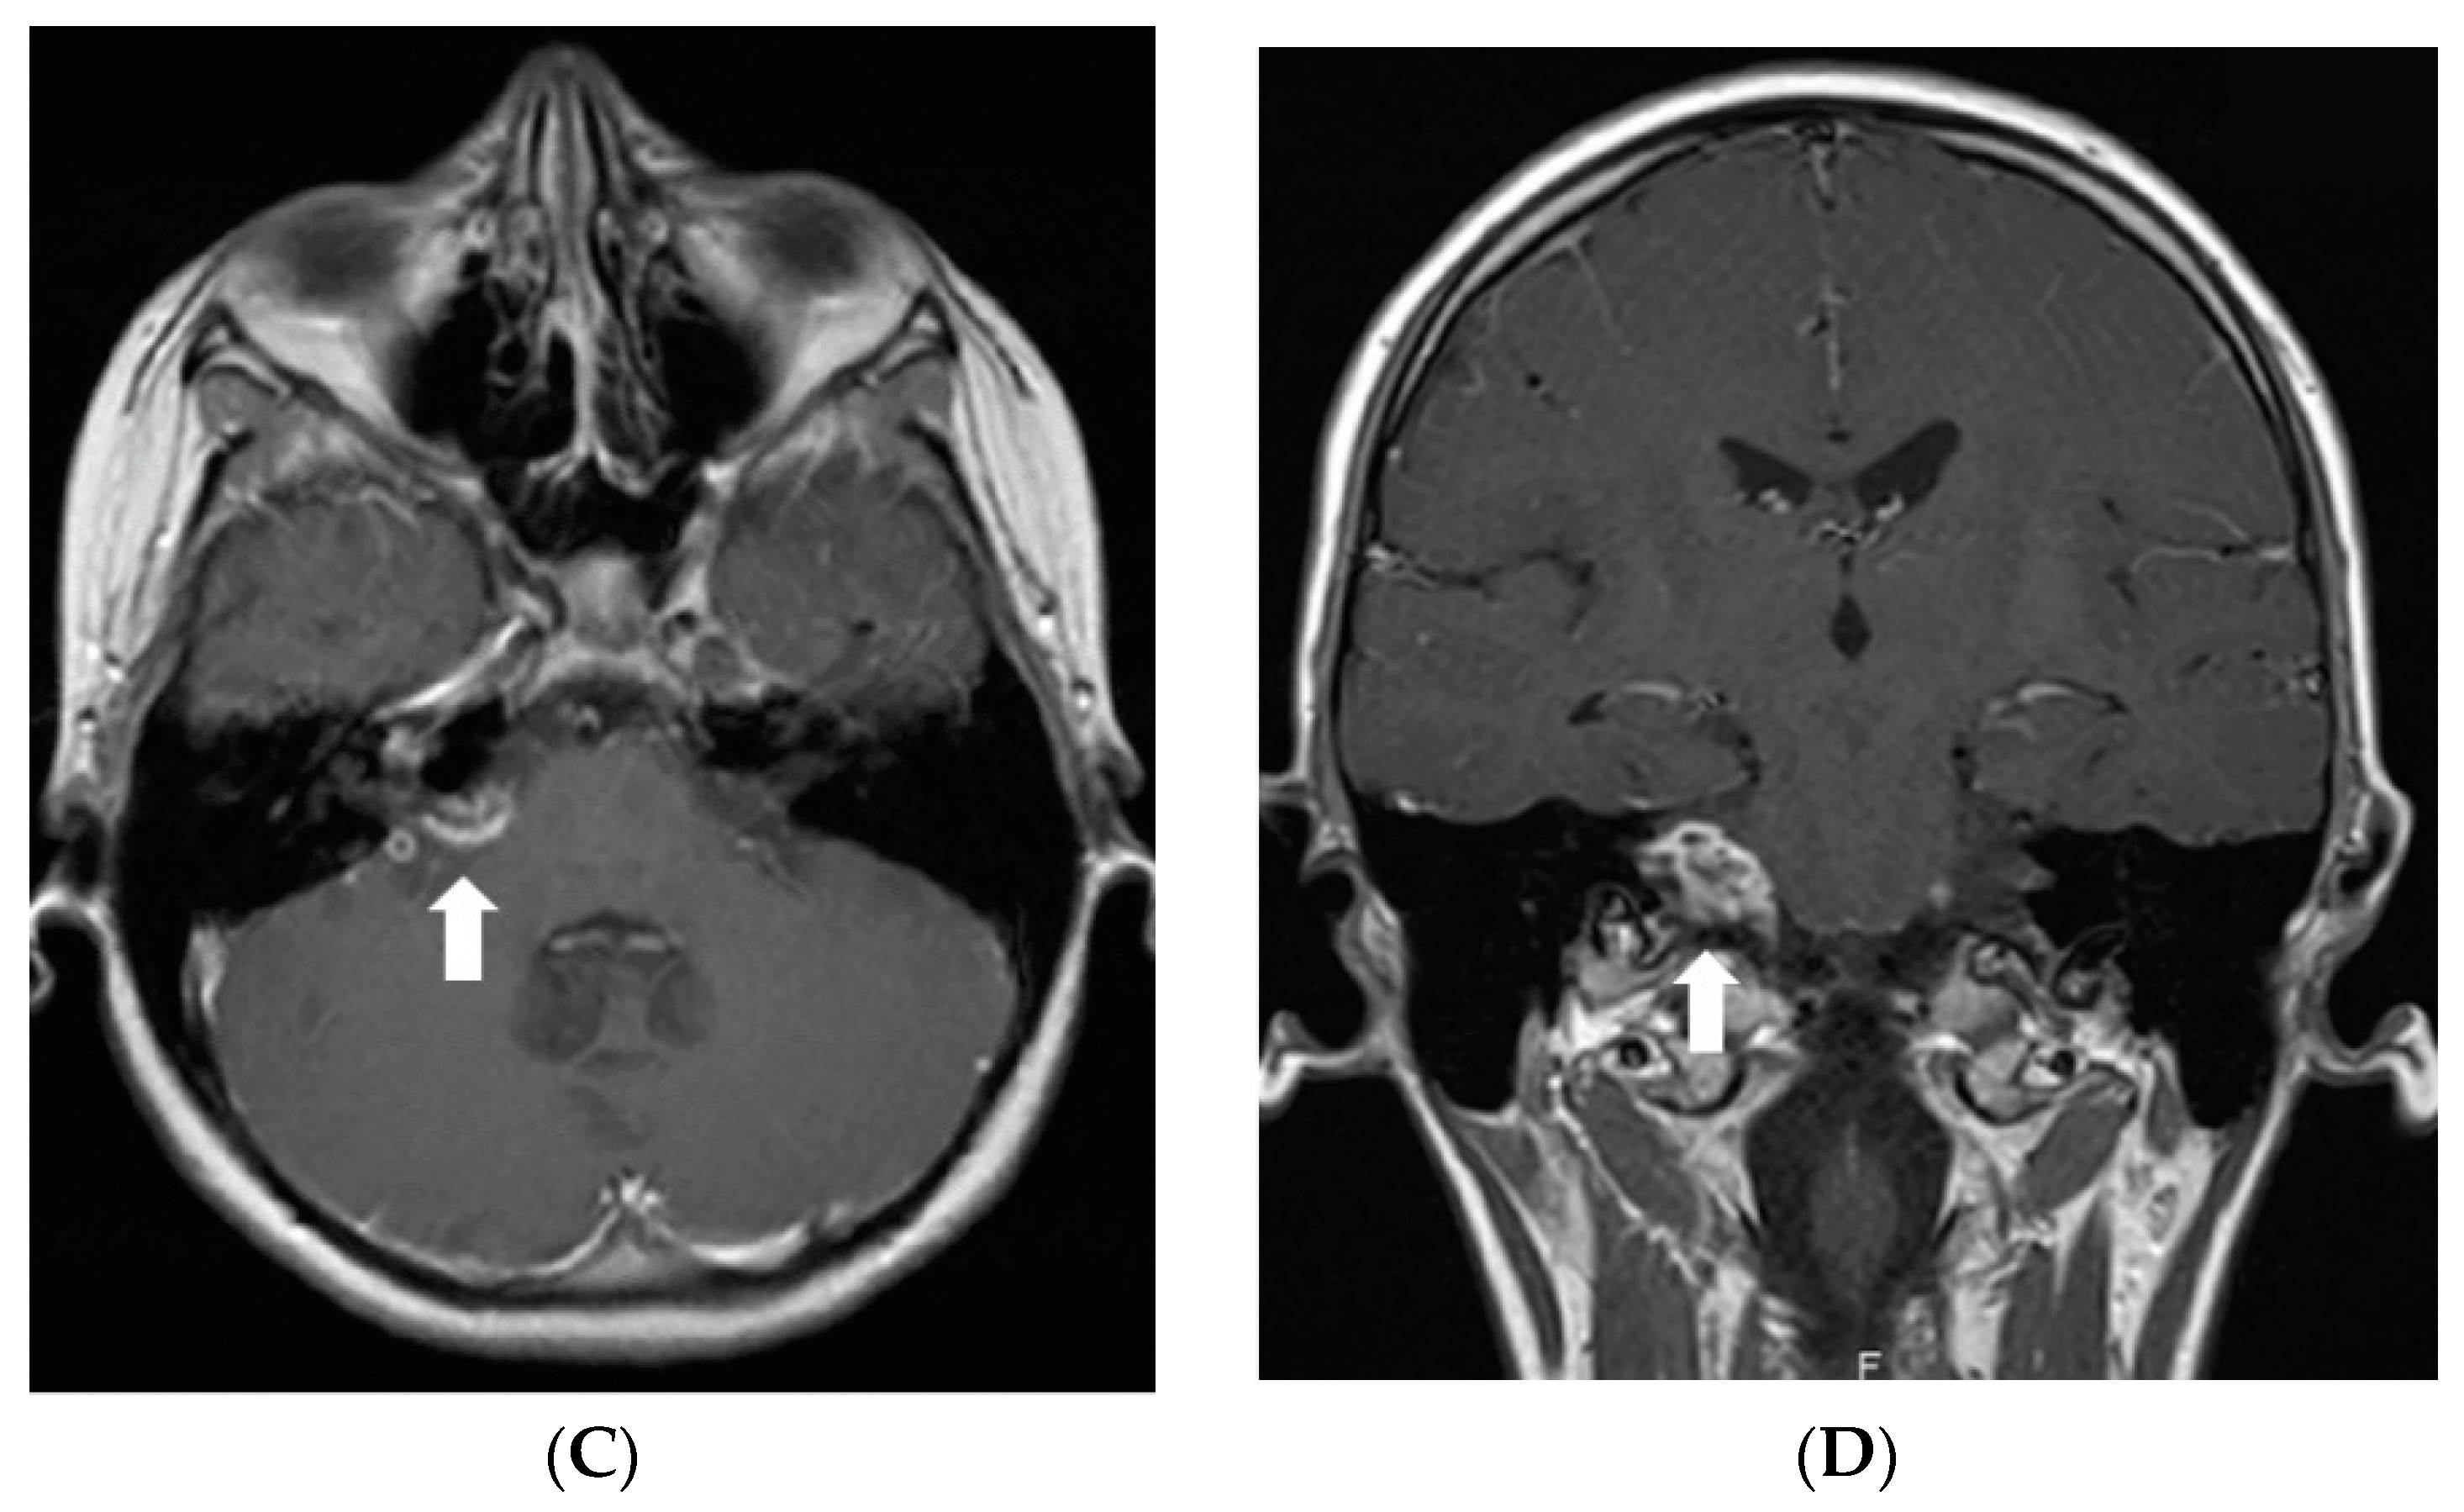

Figure 1.

Initial MRI of the brain at our clinic (July 2011): (A) Axial T2W/FLAIR and (B) coronal T2W images demonstrate a hyperintense mass in the right cerebellopontine angle cistern and internal auditory canal. (C) Axial and (D) coronal T1W postcontrast images show heterogenous enhancement in the referred area.

Five months after the first MRI, another MRI was performed, and it showed a new small enhancing nodule in the prepontine cistern at the pontomedullary junction, in the expected location of the left abducens nerve (Figure 2).

Figure 2.

Follow-up MRI of the brain after the surgery (in December 2011). Axial post-contrast T1W image demonstrates a new enhancing nodule in the expected location of the cisternal segment of the left abducens nerve.